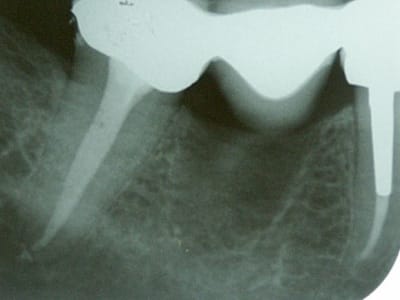

Ben voilà, j'ai fait l'endo aujourd'hui: digue, protaper, mac spadden, loupes orascoptic.

Je n'ai finalement trouvé qu'un seul gros canal dans cette fichue 47. J'ai du préparer à 45, tellement le foramen était gros. Il faisait bugger le root ZX.

Ci-jiont je vous file les radios.

La patiente est en or et a été super patiente pendant le soin.

t'as quand même eu du pot dans ton malheur,de n'avoir qu'un si gros canal,en tout cas bravo!